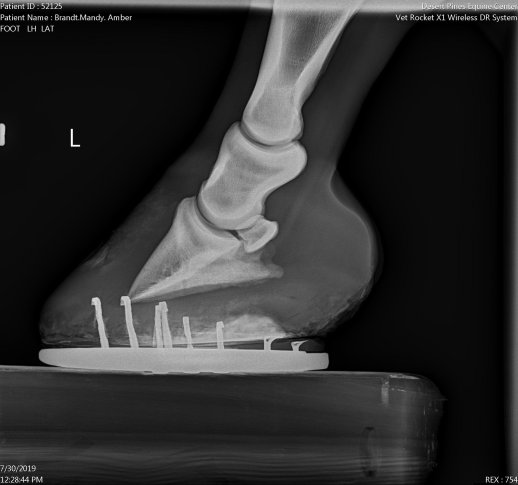

Last Amber saw the vet 8 weeks ago, she’d worn down her sole to where she was very uncomfortable, and her coffin bone was pretty straight, so she needed a wedge pad that could take the pressure off of her back tendon. So, she got a full set of shoes again, and my farrier lopped off all of that extra toe. More could still come off, but obviously there’s only so far you can take a hoof down in one trimming.

But her x-rays and feet went from looking like this:

To looking like this:

You can bet I’m feeling pretty damn good about that. Just a big breath of relief. Looks like we’ve found a perfect angle, and having shoes on the hind feet and a pad is all just the right mix for her. That’s A LOT of sole that she grew, which is super positive. Even Doc said that in all her x-rays she’s never grown this much hoof, which is excellent. A definite “yes” that we’re on the right track again! I know she’s happy – she really really hated those boots lol.